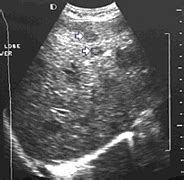

Each case is different and your doctor will explain your treatment options. There can be more than one sentinel node. It can detect head and neck cancer, determine if it has spread, assess the effectiveness of a treatment plan and determine if the cancer has returned after treatment. Ultrasound is relatively quick and simple test that gives very useful information about the soft tissues in the head and neck region including the lymph glands, salivary glands, thyroid gland and any abnormal lumps. If this happens, it is called metastasis. Ultrasound is often one of the first line tests in the detection of cancer. When ultrasound is performed on a patient with nodular goiter, or a patient with a history of thyroid cancer, finding a prominent lymph node with a rounded shape (long/short axis ratio < 2) and absent hilar line warrants further evaluation of the node (figs. An ultrasound may show your doctor if a lump is filled with fluid or if it's solid.

In my experience an ultrasound won't tell you if you have cancer, it just shows a lump. Imaging tests show pictures of the inside of the body. It can be helpful in other areas of the body as well, such as the head and neck area. The expert ultrasonographer will look for multiple changes. An ultrasound may show your doctor if a lump is filled with fluid or if it's solid. Additionally, how do they test for thyroid cancer? An ultrasound does not have the resolution to see cancer cells. Ultrasound is also used to image the abdominal organs and kidneys, which may be affected by enlarged lymph nodes. Thyroid nodules that are hypervascular, hypoechioc, or contain calcifications on ultrasound are more likely to be malignant. The most common warning sign for neck cancer is a lump in the neck. Therefore, the cause of the cancer in the neck depends on the specific type of the primary cancer. When ultrasound is performed on a patient with nodular goiter, or a patient with a history of thyroid cancer, finding a prominent lymph node with a rounded shape (long/short axis ratio < 2) and absent hilar line warrants further evaluation of the node (figs. The image of your thyroid and any nodules, even those you can't feel, will show up on a computer screen.

A neck ultrasound can be used to observe the thyroid gland to look for nodules, growths, or tumors. In this type of scan, doctors use a small camera to look at the body organs. The most common warning sign for neck cancer is a lump in the neck. For neck or thyroid mass see ent. If an ultrasound would image a tumor in the throat as well as the neck above the collar bone it would be pointless to have another procedure done. Detecting thyroid nodules that require a biopsy. Ultrasound is widely available an is useful to identify abnormal lymph nodes that may contain cancer. While it can't diagnose cancer, it can detect the abnormal tissues that may possibly be cancerous. Additionally, how do they test for thyroid cancer? Ultrasounds don't work properly with obsese patients. The camera remains attached either to a flexible tube called endoscope or to a probe, while it passes within an opening in your body, often your mouth. The most common place for head and neck cancer to spread to is the lungs. Ultrasound is often one of the first line tests in the detection of cancer.